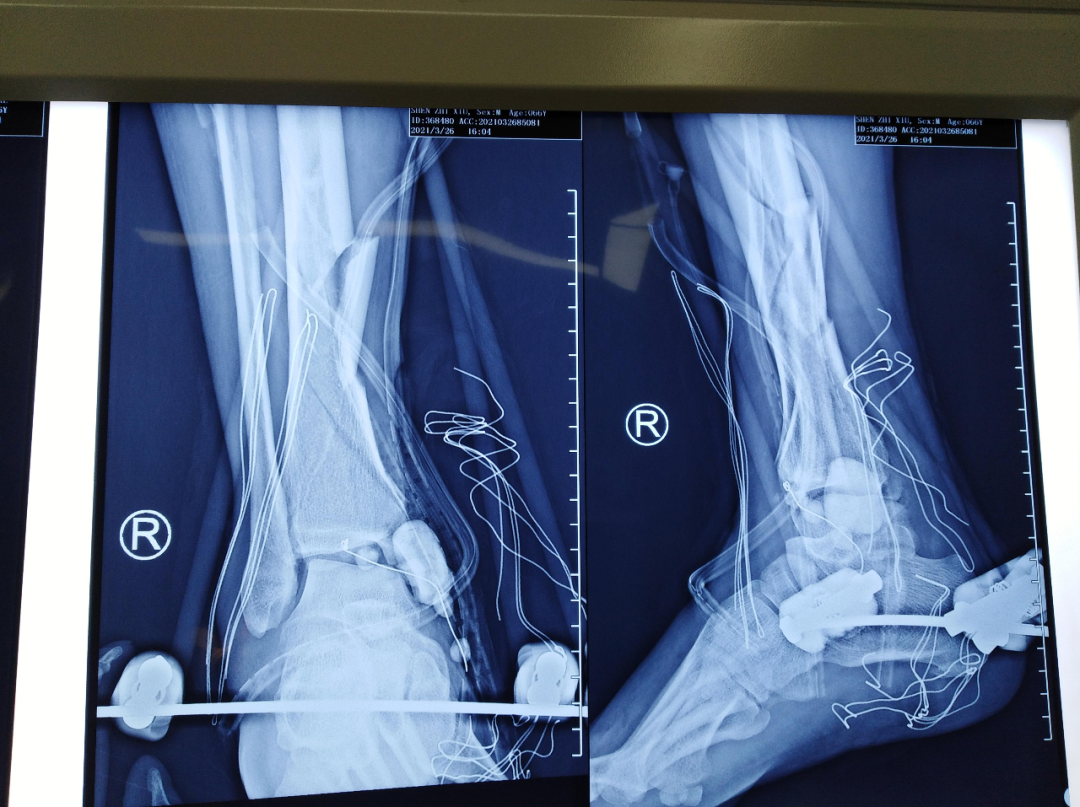

术前平片

第一次手术拍片

第二次手术拍片